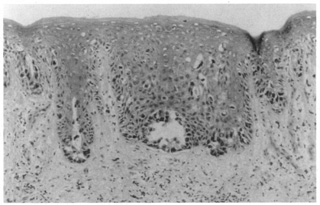

Histologic findings in normal periorbital skin are similar to other areas of the body with a keratinizing epidermis and a prominence of sebaceous glands and blood vessels (Fig. 1, A and B). Lid skin is very thin, its epidermis is composed of only a few layers of keratinocytes (squamous cells), there is an absence of the typical rete ridge (digitated) pattern, and there is a sparse dermis composed of fine fibrillar collagen fibers. Virtually every inflammatory dermatosis and cutaneous neoplasm may, at times, affect the periorbital skin and lids, but some inflammatory processes and neoplasms are commonly seen in this area, and a few are quite specific to the area.

Fig. 1. A. Photomicrograph of normal periorbital skin. B. Schematic of normal periorbital skin.